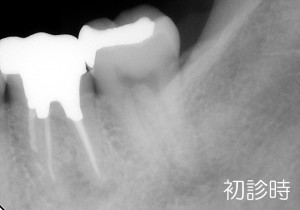

こちらの患者さんは、初診で来院された際に「かぶせ物をした当初から違和感があること、風邪を引いた時には痛むこともある」と訴えておりました。

通法に従い診査をしたところ根の病気の症状を呈しており、かぶせ物の適合が悪いこと、レントゲン写真でも根の先に怪しい像が出ていましたので、根管治療を行うことにしました。